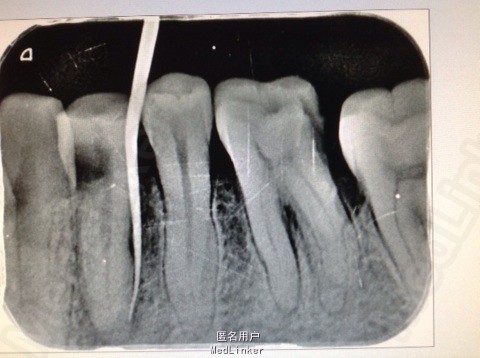

主诉:患者左下后牙胀痛数日。 病史:数日来,患者左下后牙食物嵌塞,近日疼痛不适影响进食,来院就诊。

查体:34牙合面无龋坏,探(-),冷热诊疼痛不明显,叩(+),颊侧可以可以看到窦道,X线示近中龋坏龋坏深达牙髓腔。远中及根尖有透色区。

诊断:34根尖周炎 治疗: 局麻下34去腐,开髓揭髓顶降牙合,冲洗髓腔,拔髓疏通根管,测量根管镍钛器械进行根管预备,低浓度次氯酸钠进行根管的冲洗化学预备,吸潮纸尖拭干根管,氢氧化钙进行诊间根管封药,对牙周进行洁治刮治,患者观察一周复诊,窦道明显的闭合,患者无不适感叩(-),去除暂封物进行根管试尖,X线示恰充,进行热牙胶垂直加压连续波充填法进行根管充填。暂封观察进行嵌体修复。